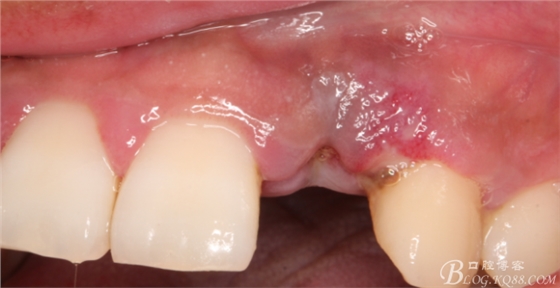

10天拆線一切正常,又過了兩周患者復(fù)診,自述期間無異常。口內(nèi)檢查,真的嚇了一跳,唇側(cè)鼓了個(gè)包,擠壓有白色分泌物溢出,絕對(duì)不是膿液,液體排除后,術(shù)區(qū)觸診空虛,外觀塌陷。這時(shí)候考研大夫的時(shí)刻到了,是先觀察一段時(shí)間再說?還是馬上進(jìn)行處理?我的回答是:馬上處理!如果你沒有及時(shí)處理,而是放患者回家觀察,那么接下來會(huì)發(fā)生如下情況:1.回家后患者家屬及親友會(huì)有很多你可以想象得到的討論;2.患者及家屬會(huì)對(duì)你產(chǎn)生不信任,勢(shì)必會(huì)到其他門診或醫(yī)院檢查,他院大夫會(huì)不會(huì)發(fā)表對(duì)你不利的言論;3甚至?xí)蚁嚓P(guān)法律界人士找你討要說法。